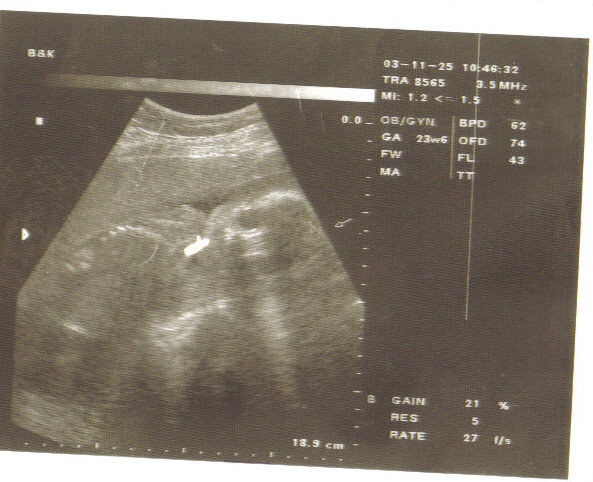

Ez az en kicsi fiam 17 hetesen. Latszik a futykos is!

NEM A MOSTANI ULTRAHANG! Meg mielott osszekavarodnatok! :lol: